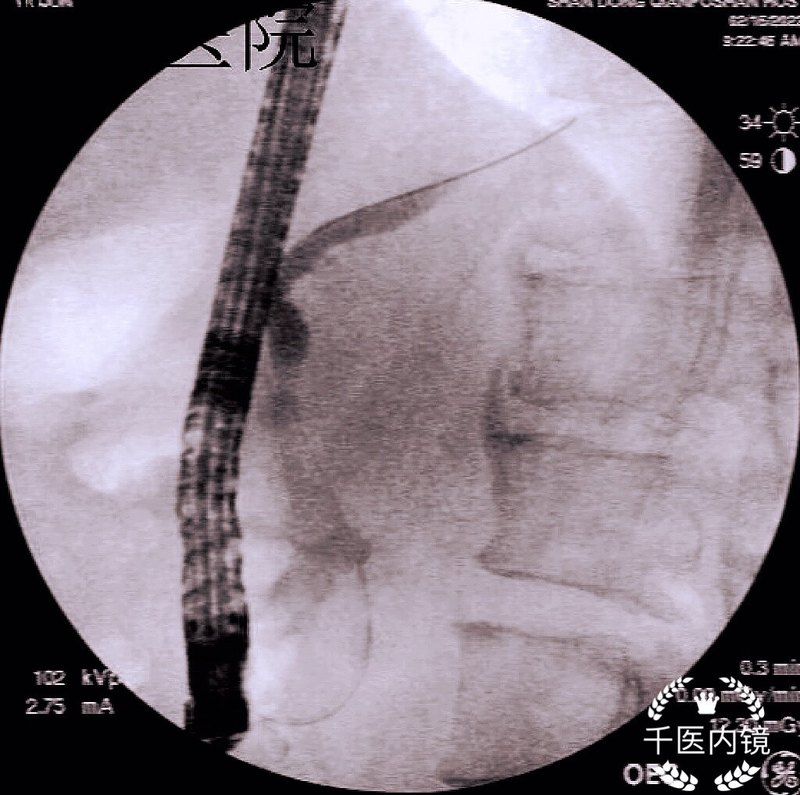

ERCP聯(lián)合腔內(nèi)碎石成就胰管頑石微創(chuàng)新攻略

慢性胰腺炎(chronicpancreatitis,CP)是由多種因素引起的胰腺組織進(jìn)行性慢性炎癥疾病,病理表現(xiàn)為胰腺腺泡萎縮、破壞和間質(zhì)纖維化。臨床癥狀上可為反復(fù)發(fā)作的上腹部疼痛,以及糖尿病、脂肪瀉等胰腺外分泌功能不全和胰腺內(nèi)分泌功能障礙表現(xiàn),可伴有胰管結(jié)石、胰腺實(shí)質(zhì)鈣化、胰管狹窄、胰管不規(guī)則擴(kuò)張、胰腺假性囊腫形成,往往遷延不愈且處理棘手,病情的進(jìn)展將帶來頑固性疼痛和體重下降、營養(yǎng)不良等,生活質(zhì)量明顯下降,甚至可能導(dǎo)致癌變,患者多需終身治療,大大的加重了社會的公共醫(yī)療負(fù)擔(dān)。而CP的全球發(fā)病率為9.62?/10萬,死亡率為0.09?/10萬,男性患者數(shù)量大約是女性患者的2倍,其致病因素常見的有酗酒、吸煙、遺傳、高脂血癥、高鈣血癥、胰腺先天性解剖異常、胰腺外傷或手術(shù)、自身免疫性疾病等,隨著社會發(fā)展及生活水平、生活習(xí)慣、環(huán)境的變化,慢性胰腺炎的發(fā)病率逐年增高,因此絕對禁酒、戒煙、調(diào)整飲食結(jié)構(gòu)、避免高脂飲食往往是診療指南的首要推薦。在慢性胰腺炎患者中,胰管結(jié)石的發(fā)生率可達(dá)90%以上,具體機(jī)制至今仍未完全明確,目前經(jīng)典的胰石蛋白理論認(rèn)為,胰液中的胰石蛋白可以抑制鈣鹽結(jié)晶的形成和生長,關(guān)鍵在于它能夠螯合碳酸鈣的活性部位,而CP患者胰腺細(xì)胞和胰管腔內(nèi)中存在胰石蛋白濃度在各種致病因素作用下降低,使得胰液中的碳酸鈣過飽和后析出沉淀,最終形成結(jié)石。結(jié)石的形成會導(dǎo)致胰液排出受阻、胰腺實(shí)質(zhì)高壓和局部缺血,引起頑固性胰源性疼痛和胰腺內(nèi)外分泌功能減退,因此徹底有效地去除胰管結(jié)石、通暢胰管引流可以大大緩解CP患者腹痛等癥狀,明顯提高生活質(zhì)量,并降低胰腺炎再發(fā)及胰腺癌發(fā)生的風(fēng)險。慢性胰腺炎合并胰管結(jié)石微創(chuàng)治療主要是指介入方面,內(nèi)鏡逆行胰膽管造影術(shù)(ERCP)和(或)胰腺體外震波碎石術(shù)(P-ESWL)為一線治療方法,相比較開刀手術(shù)而言,具有創(chuàng)傷小、恢復(fù)快、住院時間短等優(yōu)勢,大大提高了患者的生活質(zhì)量。根據(jù)能否透過X線將結(jié)石分為陽性結(jié)石與陰性結(jié)石,陰性結(jié)石或最大徑<5mm的陽性結(jié)石可通過ERCP取出,最大徑>5mm且位于胰頭或胰體的陽性結(jié)石應(yīng)行P-ESWL將結(jié)石充分粉碎(直徑=5mm的結(jié)石視具體情況選擇治療方案)。然而準(zhǔn)確定位結(jié)石是ESWL期間的一項(xiàng)重大挑戰(zhàn),因?yàn)榻Y(jié)石可能在呼吸周期中進(jìn)出,導(dǎo)致沖擊從結(jié)石傳遞到胰腺實(shí)質(zhì),使患者可能出現(xiàn)急性胰腺炎、消化道出血、穿孔、感染、石結(jié)(結(jié)石碎裂后堵塞胰管遠(yuǎn)端,導(dǎo)致胰液流出障礙胰管壓力急劇升高,患者出現(xiàn)難以緩解的腹痛)等并發(fā)癥。???近年來,隨著ERCP子母鏡技術(shù)的發(fā)展,腔內(nèi)碎石術(shù)在臨床的應(yīng)用越來越廣泛,對于無法開展P-ESWL或經(jīng)P-ESWL充分碎石后結(jié)石仍未碎裂的患者,可考慮行胰管腔內(nèi)碎石術(shù),常用的腔內(nèi)碎石術(shù)有機(jī)械碎石術(shù)(ML)、液電碎石術(shù)(EHL)和激光碎石術(shù)(LL)。南陽市中心醫(yī)院胰腺外科ERCP團(tuán)隊(duì)秉承“鏡”益求精的理念,在省內(nèi)率先同時開展體外震波碎石和胰管腔內(nèi)碎石,在近年內(nèi)已成功治療了多位慢性胰腺炎合并胰管結(jié)石的患者,傳統(tǒng)的P-ESWL后患者若無法自發(fā)排石,則需再行ERCP取石,而團(tuán)隊(duì)借助子母鏡技術(shù)和腔內(nèi)碎石術(shù)的應(yīng)用,能夠做到在直視下觀察結(jié)石,準(zhǔn)確定位,并且結(jié)石碎裂后直接取石,大大減少了操作步驟和醫(yī)療費(fèi)用,其微創(chuàng)、安全、高效等優(yōu)勢,使得在治療胰管結(jié)石中的價值日益突出。胰腺外科劉馳主任表示,團(tuán)隊(duì)也將繼續(xù)深入研究學(xué)習(xí)國內(nèi)外先進(jìn)技術(shù)經(jīng)驗(yàn),不斷探索慢性胰腺炎的診治新方法,為廣大胰管結(jié)石患者帶來福音。

胰管結(jié)石是慢性胰腺炎常見并發(fā)癥。根據(jù)分布位置,分為I型,胰頭部,II型胰體部,III型胰尾部,IV型廣泛分布。病因多種,飲酒,慢性胰腺炎,膽管疾病,膽道蛔蟲,營養(yǎng)不良,甲旁亢,遺傳,高鈣血癥等。癥狀主要有腹痛、脂肪瀉、糖尿病、黃疸等。治療主要是內(nèi)鏡治療,外科手術(shù)等。內(nèi)鏡治療包括ERCP取石,體外沖擊波碎石(ESWL),機(jī)械碎石,液電碎石,激光碎石等。胰管結(jié)石質(zhì)地較硬,網(wǎng)籃取石有嵌頓的風(fēng)險,spyglass直視下激光碎石有明顯的優(yōu)勢,微創(chuàng),費(fèi)用低,術(shù)程簡單,康復(fù)快速。